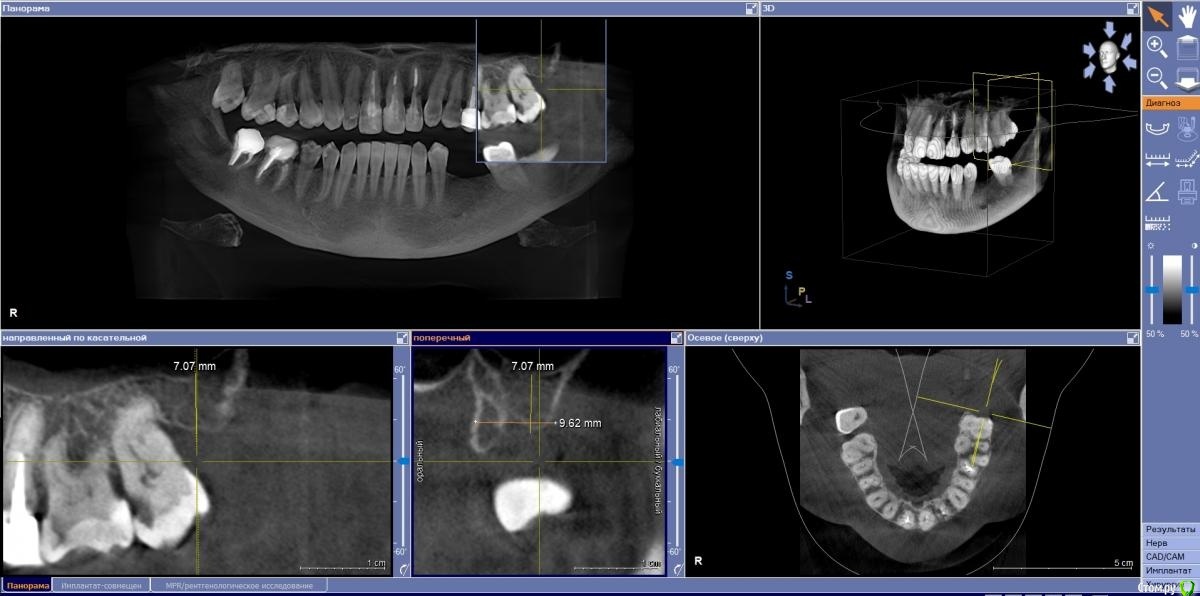

Fin Опубликовано 4 ноября, 2020 Поделиться Опубликовано 4 ноября, 2020 (изменено) Здравствуйте коллеги. В клинику обратилась пациентка с жалобой на эстетику передних зубов. В ходе осмотра и составления плана на КТ обнаружилась резка корня 22. Перфорация вестибулярной стенки на КТ не наблюдается. Думаю что при полном удалении корня вестибулярная стенка тоже уйдет. Техника IDR и B2S невозможна т.к. присутствуют восьмые зубы.Как вы считаете, стоит ли попытка сделать одномоментную имплантацию с техникой вариантов корневого щита или все таки идти на полное удаление? Изменено 4 ноября, 2020 пользователем Fin Ссылка на комментарий

Дмитрий М Опубликовано 8 ноября, 2020 Поделиться Опубликовано 8 ноября, 2020 судя по снимку щит не получится, по причине его отсутствия 1 Ссылка на комментарий

Fin Опубликовано 9 ноября, 2020 Автор Поделиться Опубликовано 9 ноября, 2020 судя по снимку щит не получится, по причине его отсутствия Благодарю за ответ. Будем делать классику. А я думал наоборот пол дела сделано)) Х. Глюкман говорил что лучше немного подпилить корень в глубину, что бы не прорезался. Хотя тут не два мм а 4. Ссылка на комментарий

Евгений Ходыкин Опубликовано 10 ноября, 2020 Поделиться Опубликовано 10 ноября, 2020 Нет тут места и на щит, и на имплантат Ссылка на комментарий

Fin Опубликовано 10 ноября, 2020 Автор Поделиться Опубликовано 10 ноября, 2020 (изменено) Нет тут места и на щит, и на имплантатНе понял Вас. Между корнями около 8 мм , 3.5 должен пройти. Больше беспокоит что после полного удаления корня образуется перфорация кортикальной стенки. Изменено 10 ноября, 2020 пользователем Fin Ссылка на комментарий

Евгений Ходыкин Опубликовано 11 ноября, 2020 Поделиться Опубликовано 11 ноября, 2020 Не понял Вас. Между корнями около 8 мм , 3.5 должен пройти. Больше беспокоит что после полного удаления корня образуется перфорация кортикальной стенки.В вестибуло-оральном направлении имею ввиду Ссылка на комментарий